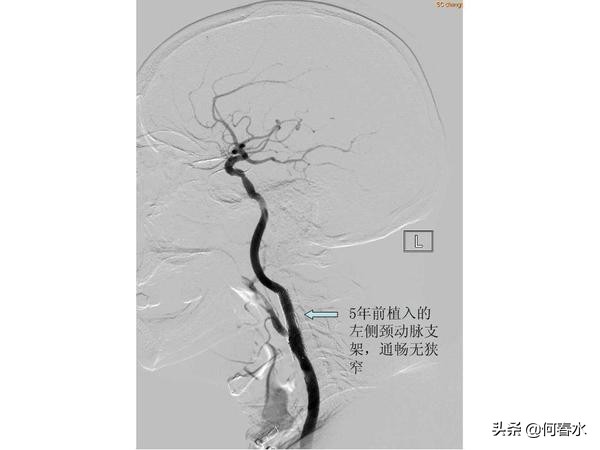

患者至今随访5年,支架通畅,头晕等脑缺血症状完全消失。但是春节后再次出现头晕不适,在职工医院检查发现右侧颈动脉重度狭窄,右侧颅内梗塞病灶,左侧颅内未有梗塞病灶。入住我科后,造影检查发现:右侧颈动脉重度狭窄伴有溃疡形成,左侧颈动脉支架通畅,右侧肾动脉重度狭窄。

(2)颈动脉支架预防脑梗塞的有效性:患者5年前左侧颈动脉重度狭窄,左侧颅内梗塞病灶,5年来植入颈动脉支架通畅良好,现在CT复查未见左侧颅内梗塞病灶,有力地证明了颈动脉支架预防脑梗塞的重要作用;